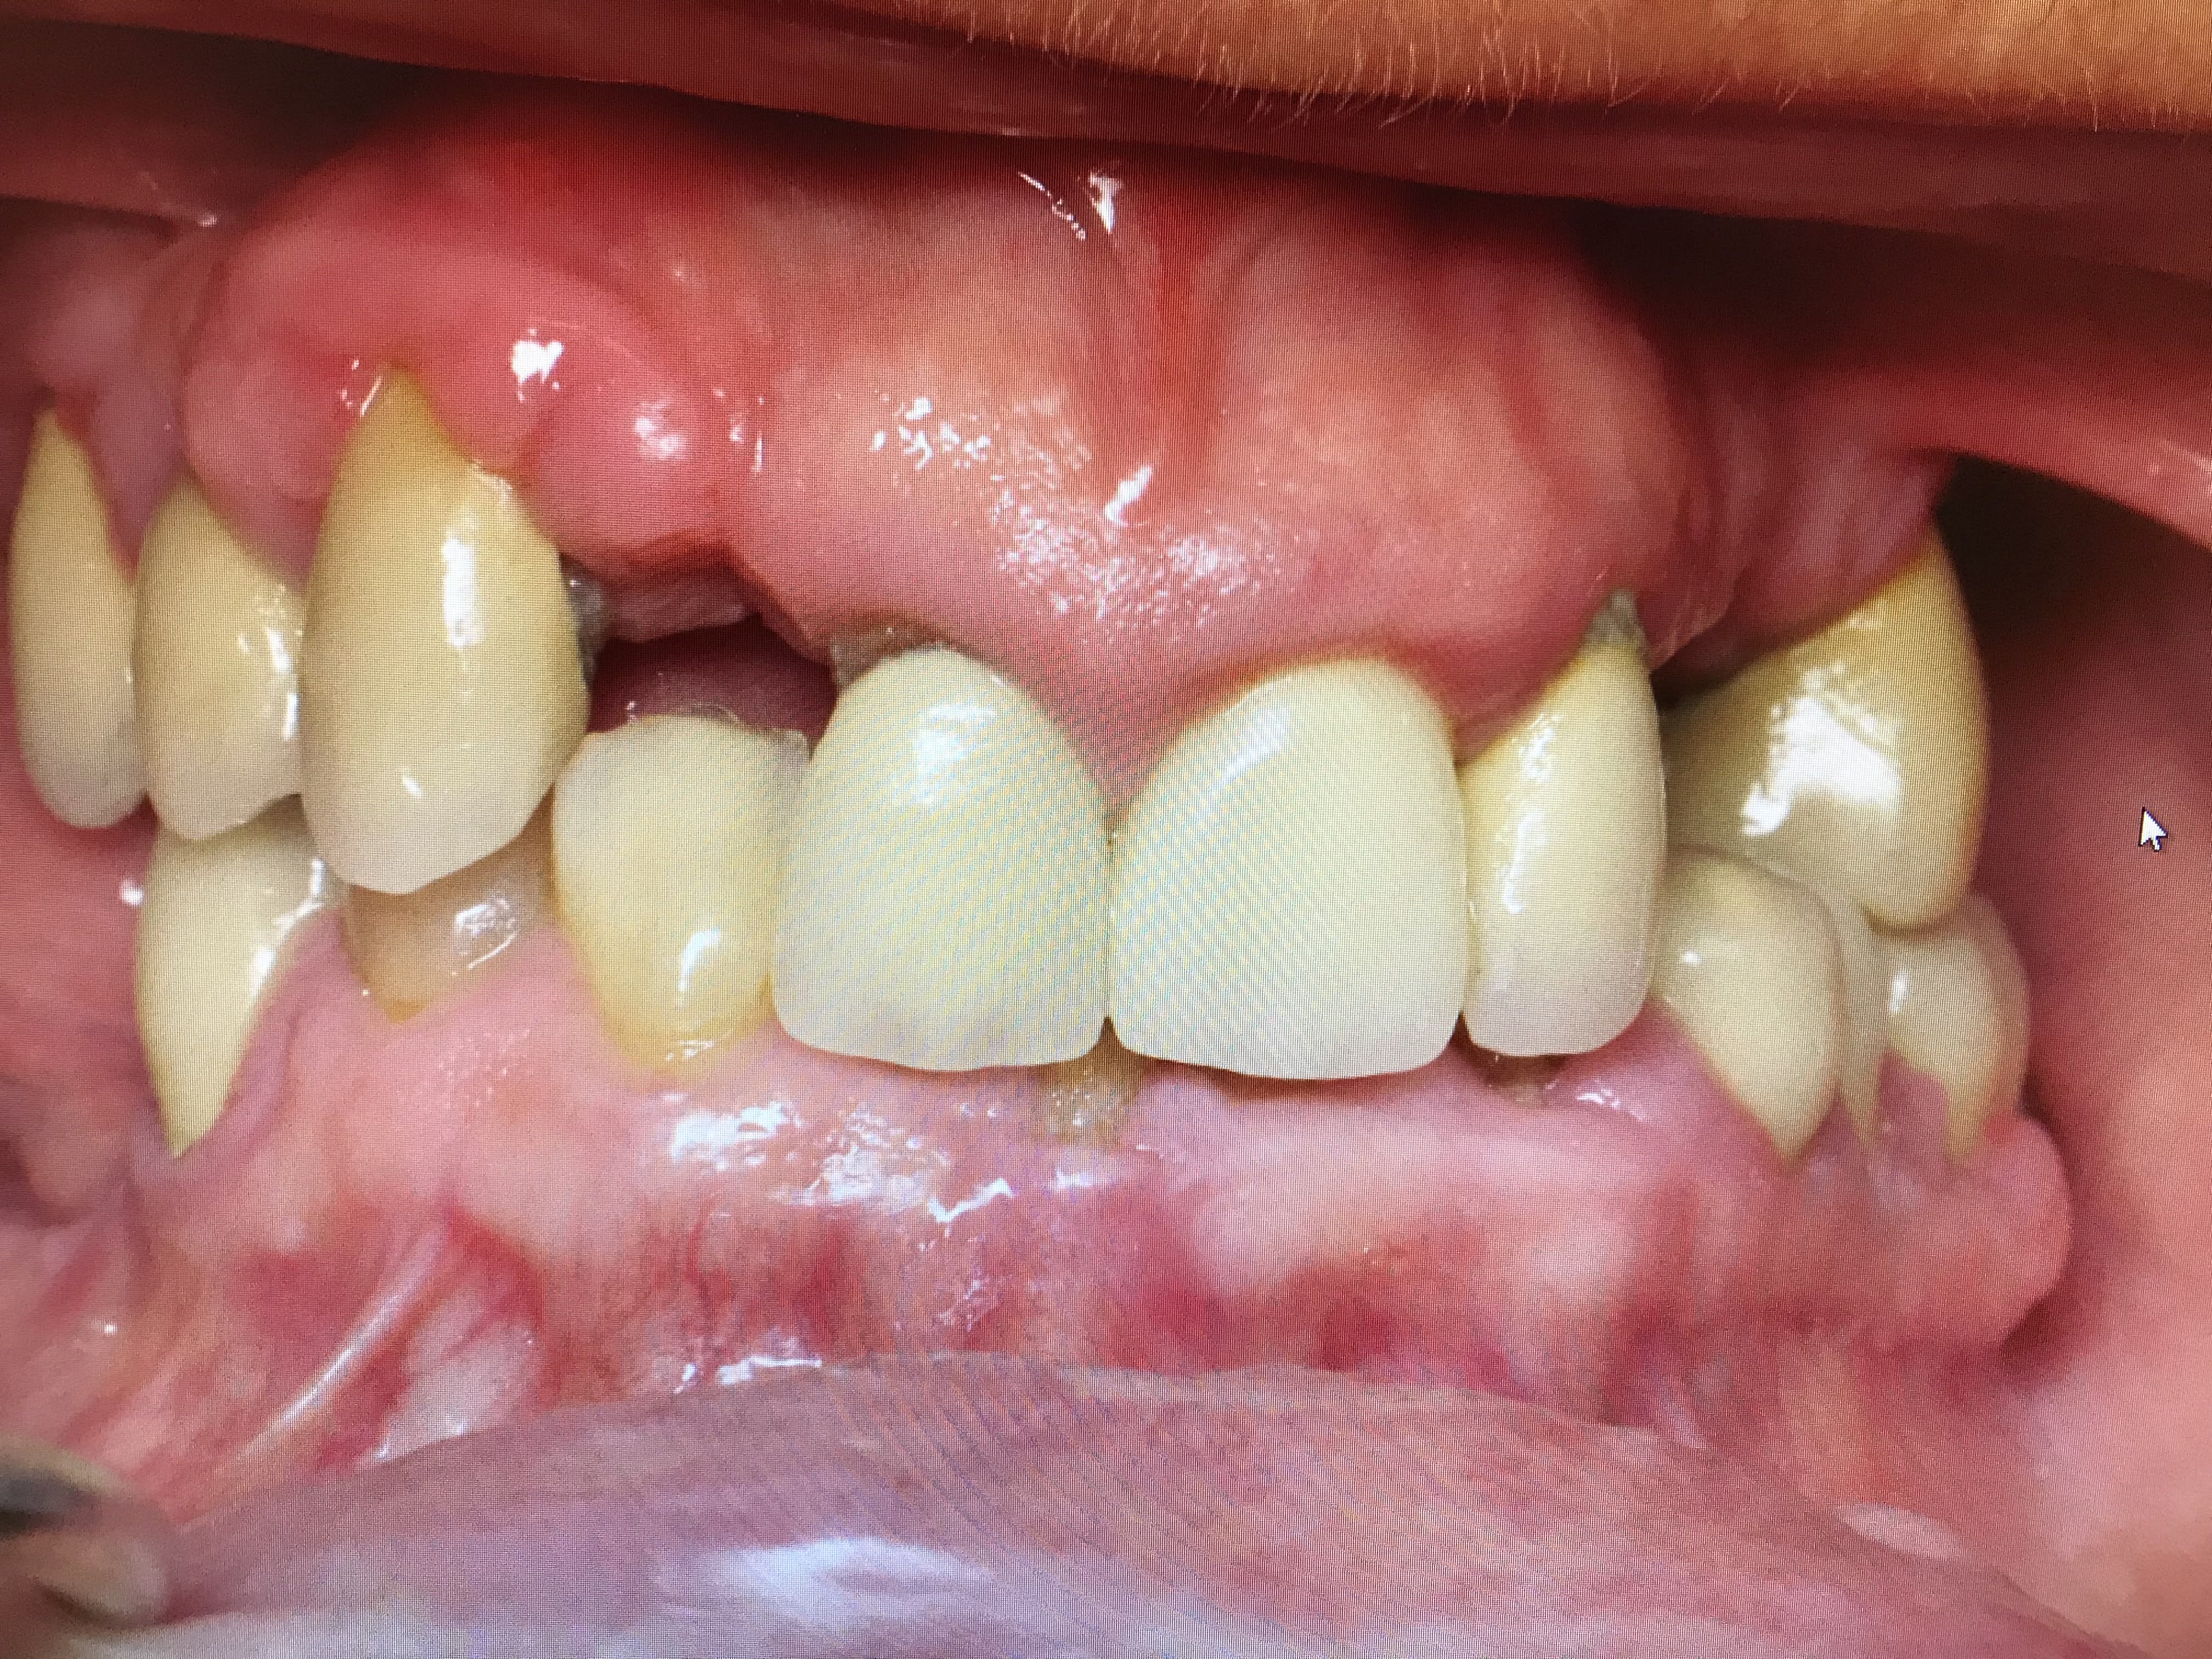

Patiente avec pilier de bridge 13 fracturé + 15 paro mobile + 25 paro mobile + 22 légèrement mobile. Les seules dents "viables" sur l'arcade sont 11, 21 et 22 et la 12 a été extraite entre temps.

Patiente avec grosse supraclusion et sourire gingival.